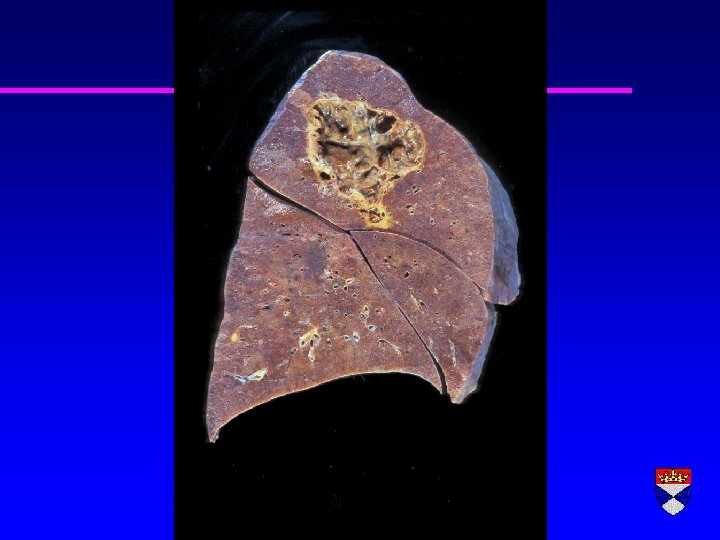

Pummonary Embolus

Pulmonary infarct – tumour embolus